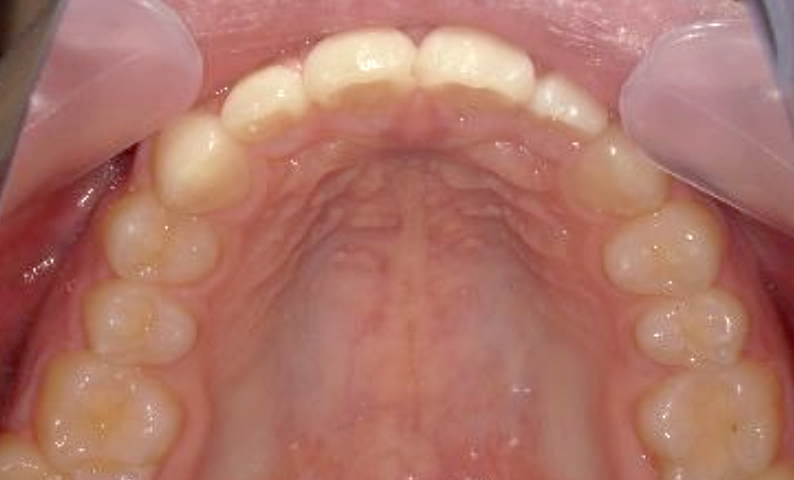

| 治療前 | 治療後 |

|---|---|

|